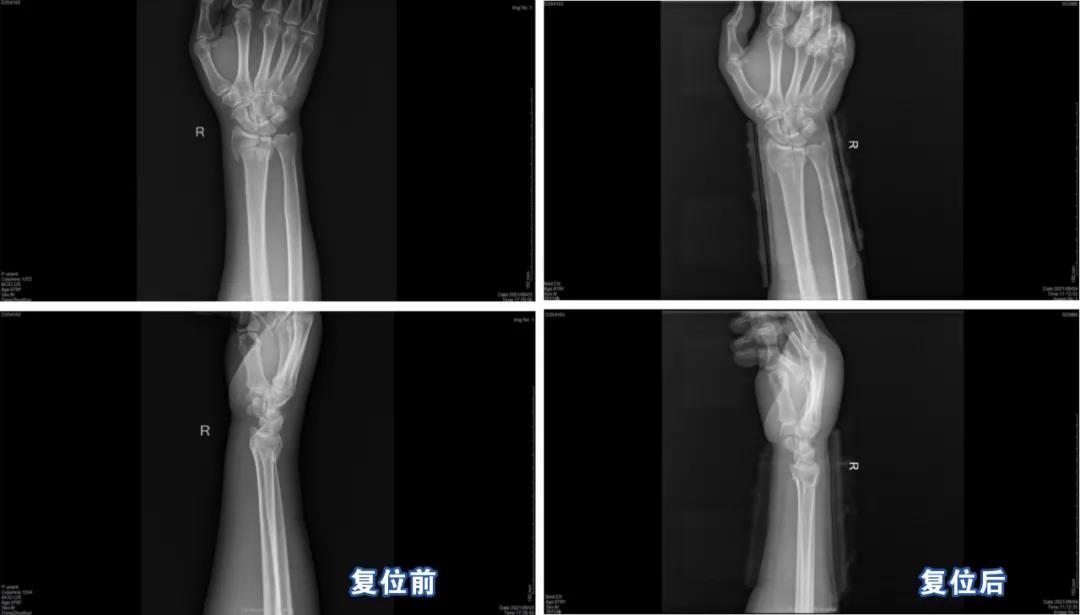

前几日,家住梧州长洲区的邓大爷在家不慎从凳子上跌倒,导致右腕部肿痛、变形,疼痛剧烈,无法移动。其家人连忙带其来到附近的医院就诊,拍X光显示,右桡骨远端粉碎性骨折,外敷药物治疗后,效果不明显,于是又辗转来到梧州市中医医院急诊科就诊。经检查诊断,患者的右侧桡骨远端粉碎性骨折,折断错位成角,下尺桡关节脱位。

小夹板外固定后,通过C臂机透视显示:右桡骨远端骨折和下尺桡关节脱位已经复位,内固定位置准确,达到预期效果。

患者返回病房后,其家属听着医生结合摄片给出的说明,顿时舒了一口气,并连声道谢,对医生们的复位技巧连连称赞。